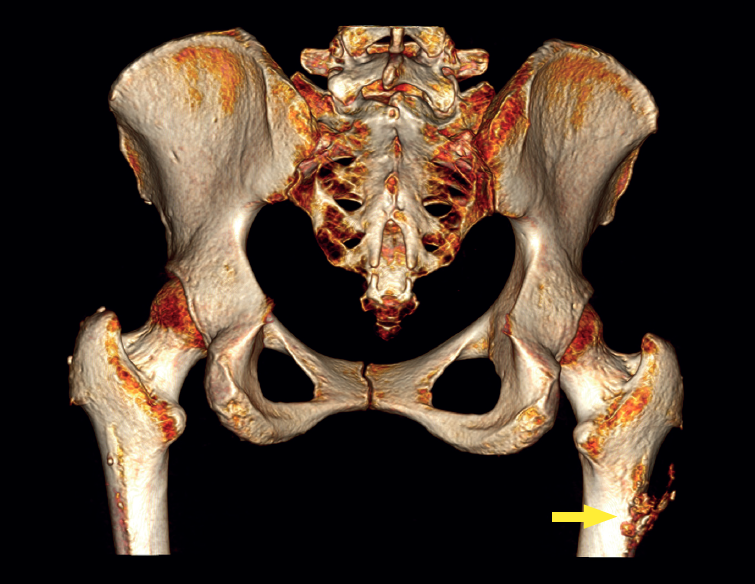

The physical examination revealed a limp-free gait and complete joint balance, with no positive signs of femoroacetabular impingement or inguinal pain. Muscle strength was preserved and similar to that of the contralateral side. She experienced intense pain on palpation of the insertion of the gluteus maximus, referred proximally to the ipsilateral buttock. The pain was reproduced on extension against resistance, and prevented sitting for long periods. Plain radiographic and computed tomography (CT) images revealed calcific tendinosis affecting the aponeurotic prolongation of the gluteus maximus in proximity to its insertion in the upper region of the linea aspera of the femur (Figures 1 and 2) Magnetic resonance imaging (MRI) of the hip showed a labral tear, that proved asymptomatic in the physical examination. In view of the clinical picture of radicular pain, an MRI scan of the lumbar spine and subgluteal space was also performed, ruling out radicular involvement or sciatic neuritis. Her previous treatment over the three years of evolution of the disorder included oral nonsteroidal anti-inflammatory drugs, a specific physiotherapy programme and several ultrasound-guided corticosteroid injections with positive results - though a last session showed no response. Due to the severity and chronicity of the symptoms and their resistance to conservative treatment, surgery was decided to clean and remove the intratendon calcification endoscopically.

A usual rehabilitation protocol after hip arthroscopy / endoscopy was applied, with crutch-assisted weight bearing for three weeks and circumduction movements plus stationary cycling for 15 minutes, four times a day. The patient was advised to avoid extension and long stride exercises in order to prevent possible gluteus maximus tendon injuries. She reported complete reversal of the symptoms, including the radicular pain, with a return to physical activity and sports three months after surgery. One year after the operation, the patient remained asymptomatic in any activity, with complete disappearance and no recurrence of the calcification (Figure 4).